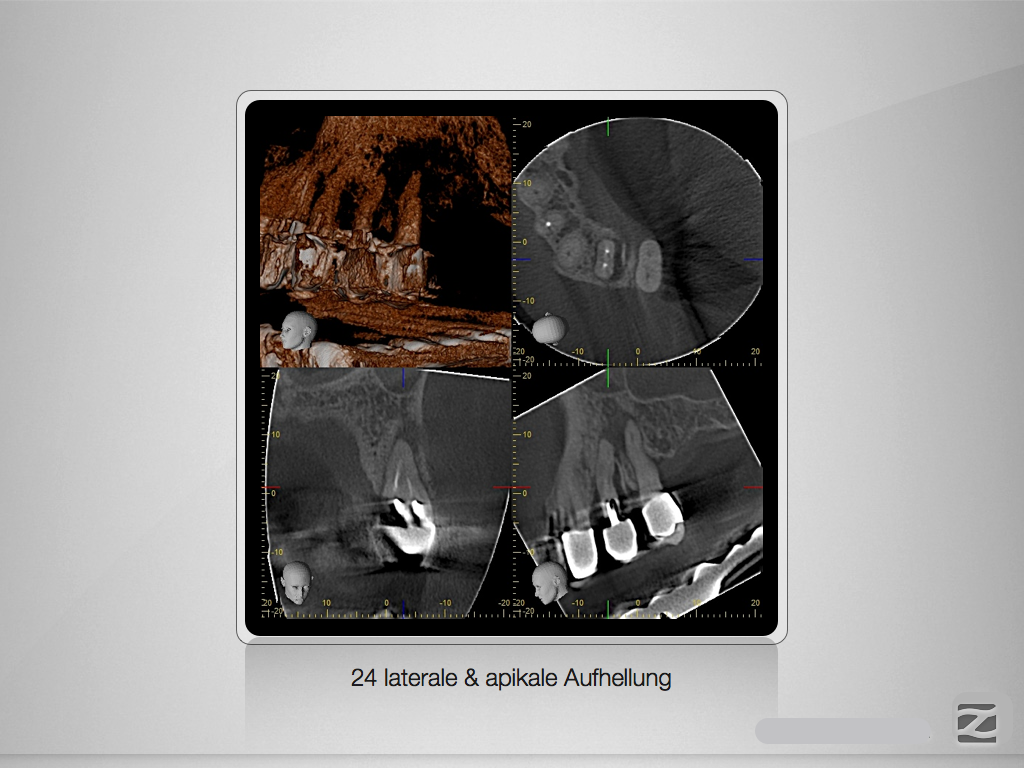

Die Offensichtigkeits-Gefahr